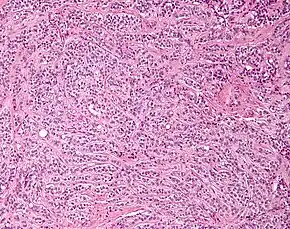

Micrograph of a granulosa cell tumour, a type of sex-cord–gonadal stromal tumour. H&E stain.

By prevalence

• Granulosa cell tumour. This tumour produces granulosa cells, which normally are found in the ovary. It is malignant in 20% of women diagnosed with it. It tends to present in women in the 50-55yo age group with post menopausal vaginal bleeding. Uncommonly, a similar but possibly distinct tumour, juvenile granulosa cell tumour, presents in pre-pubertal girls with precocious puberty. In both groups, the vaginal bleeding is due to oestrogen secreted by the tumour. In older women, treatment is total abdominal hysterectomy and removal of both ovaries. In young girls, fertility sparing treatment is the mainstay for non-metastatic disease.